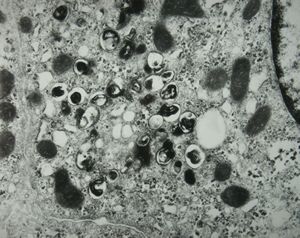

M,15y. | Wilson disease - megamitochondria

M,15y. | Wilson disease